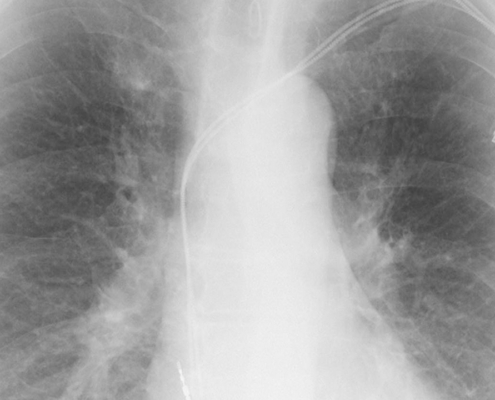

Trajni srčani elektrostimulator

Elektrostimulator srca (engl. pacemaker) je električni uređaj koji se ugrađuje ispod kože pacijenta kako bi održavao ili povratio normalan srčani ritam.